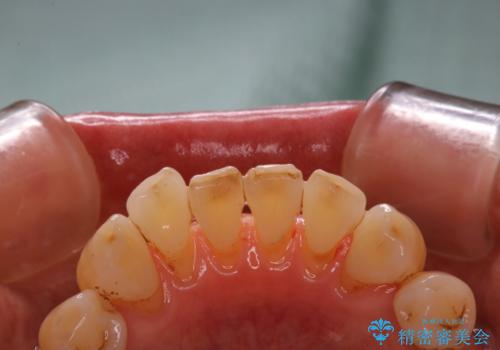

- クリーニングがかなり久しぶりで、全体的にきれいにして欲しいとのことで来院されました。全体的にステインの量がとても多かったため、施術前にご相談をし、60分コースでできる限りのステイン落としを行うこととなりました。今回は審美的に見える表側をメインでPMTCを行いました。

毎日丁寧に歯磨きをしていても、日常生活での飲食物などにより着色してしまうことはあります。PMTCでは、歯の表面の凸凹にミネラルを補給して、ツルツルの表面に仕上げます。定期的にPMTCを行うことにより、歯質の強化になり着色がつきにくい状態になります。